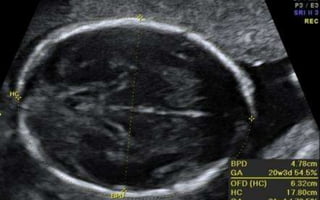

Biparietal Diameter (BPD)

• Measured after 13 weeks

• Babies of same weight can have different head size – dating

at later pregnancy is unreliable with BPD alone.

• A wrong measurement plane can produce errors up to

20mm.

• BPD remains the standard against which other parameters

of GA assessment are compared.

BPD Measurement Technique

• Measurement; Outer edge of the near cranium to the inner

edge of the far cranium.

• Middle to middle is also acceptable.

• BPD can be smaller (and sometimes much smaller than is

expected) in fetuses with flatter head (check the head

circumference).

Head Circumference (HC)

• An essential parameter for the estimation of fetal weight as

well as in cases with abnormal fetal head size (i.e.,

microcephaly/macrocephaly)

Occipito-frontal Diameter (OFD)

• Distance between the back of the head and the forehead.

• To assess the growth and development.

• an important indicator of overall fetal health and well-being.